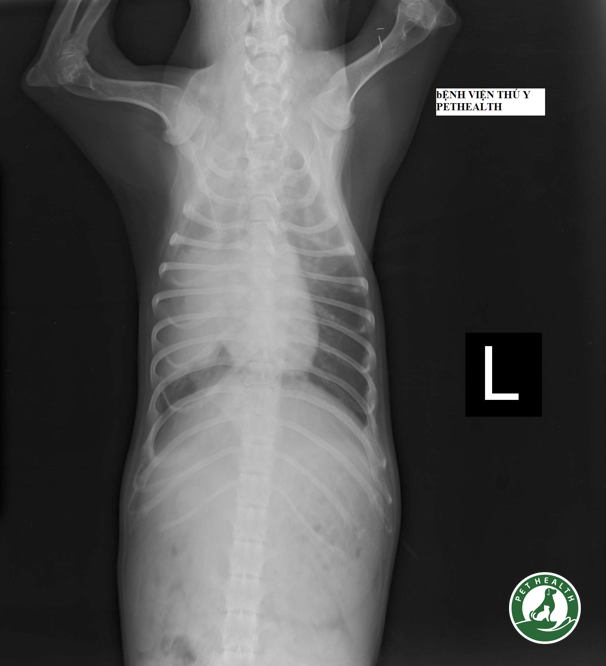

Hình ảnh X-quang ngực của một ca bệnh viêm phổi tại Bệnh viện thú y PetHealth sẽ cho thấy sự khác biệt giữa phần phổi khỏe và phần phổi viêm. Phổi khỏe mạnh chứa đầy không khí chủ yếu là màu đen với lớp màng mỏng của mô phổi. Các phần xuất hiện màu trắng đại diện cho mủ và dịch tiết trong phổi. Chú ý sự xuất hiện của “nhánh cây” tối trên vùng trắng của mô phổi. Đây được gọi là phế quản hơi và đại diện cho không khí bên trong đường thở được làm nổi bật bởi phổi bất thường chứa đầy chất lỏng xung quanh nó. Thông thường không thể nhìn thấy sự phân nhánh của đường thở vì nó nằm cạnh phổi chứa đầy không khí và hòa trộn vào.

Chẩn đoán viêm phổi không thể thiếu kỹ thuật X-quang. Bác sĩ thú y phải kết hợp các phát hiện từ lịch sử, khám lâm sàng và có thể thực hiện các liệu pháp ban đầu, sau đó chỉ định kiểm tra X quang ngay khi có thể